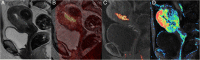

Endometrial cancer is the most common gynaecologic malignancy in developed countries and its incidence is increasing. First-level treatment, if no contraindicated, is based on surgery. Pre-operative imaging is needed for evaluation of local extent and detection of distant metastases in order to guide treatment planning. Radiological evaluation, based on transvaginal ultrasound, MR and CT, can make the difference in disease management, paying special attention to assessment of entity of myometrial invasion, cervical stromal extension, and assessment of lymph nodal involvement and distant metastases.